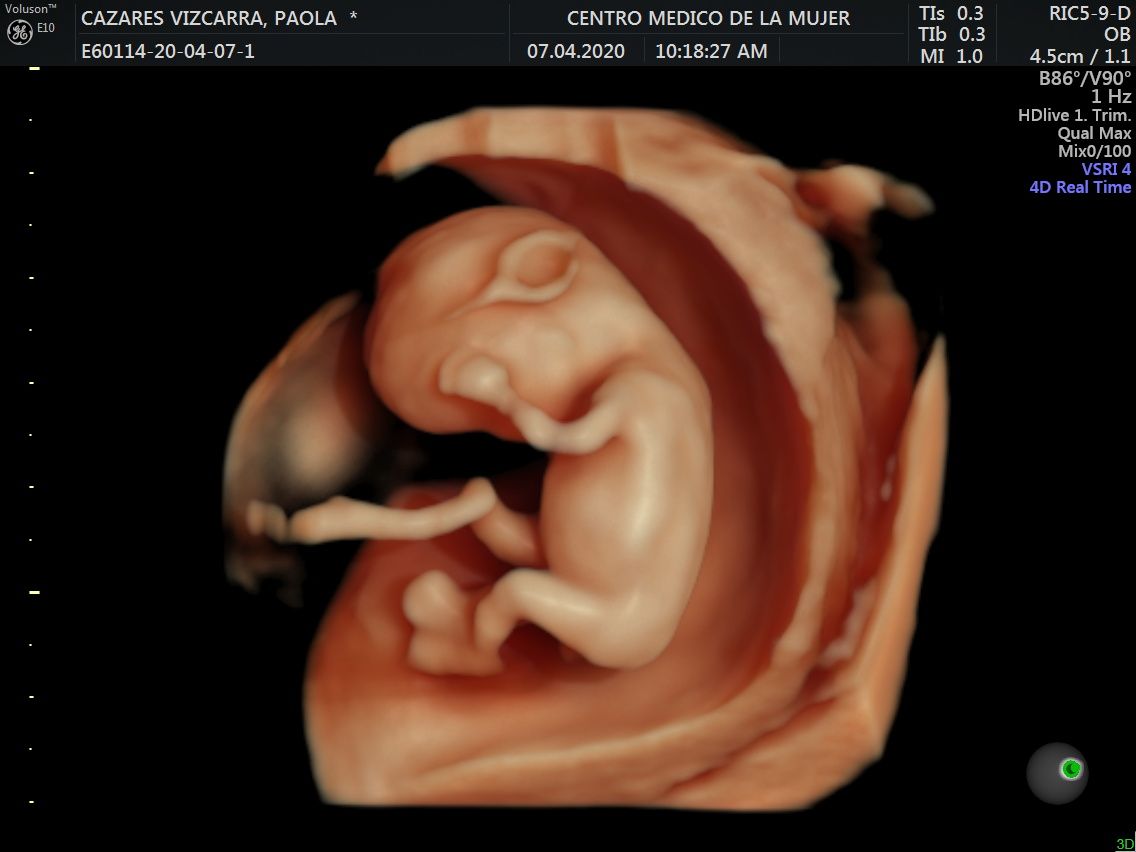

Fotos y videos

ECO Anatómico

Consiste en la evaluación especifica de cada organo y sistema del bebé con medidas detalladas de cada parte para evaluar su crecimiento proporcional.